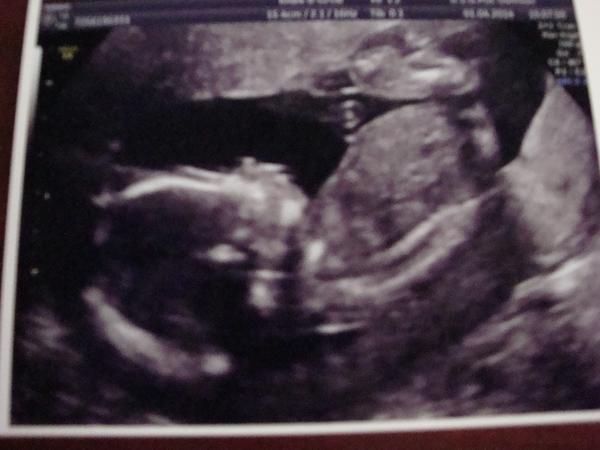

@jajinka121 Ja taky chodim k Dr. Souskove do Reprofitu,na zacatku dubna jsem poprve podstoupila IUI, i kdyz nam Dr.,ktera inseminaci provadela,moc sanci nedavala, protoze jsme meli opet horsi Spermiogram,tak ted jsem v polovine 7.tt,uz bylo videt i srdicko a doufam, ze i nadale bude vse v poradku.Drzim palce,at to take vyjdea brzy se radujete z miminka.

@carlik čauky tak my bojujem už 14dni v nemocnici na kapačkách ,měla jsem hodně vysoké ty jaterní testy tak mi to pomalu klesá,Já se citím ale dobře a prcek tak hezky roste už jsme minulý pátek měli 491gramu a je to pěkně živé miminko.Uvidíme jak dlouho si nás tady nechaji v uterý začínáme 25tt 🙂 tak jak budu mit zase notas nebo by nás pustili domů tak se ozvu pááááá 🙂

@bobulinka74 Ahojky ,no zadařilo se už začínáme 19tt 😀 😀 😀